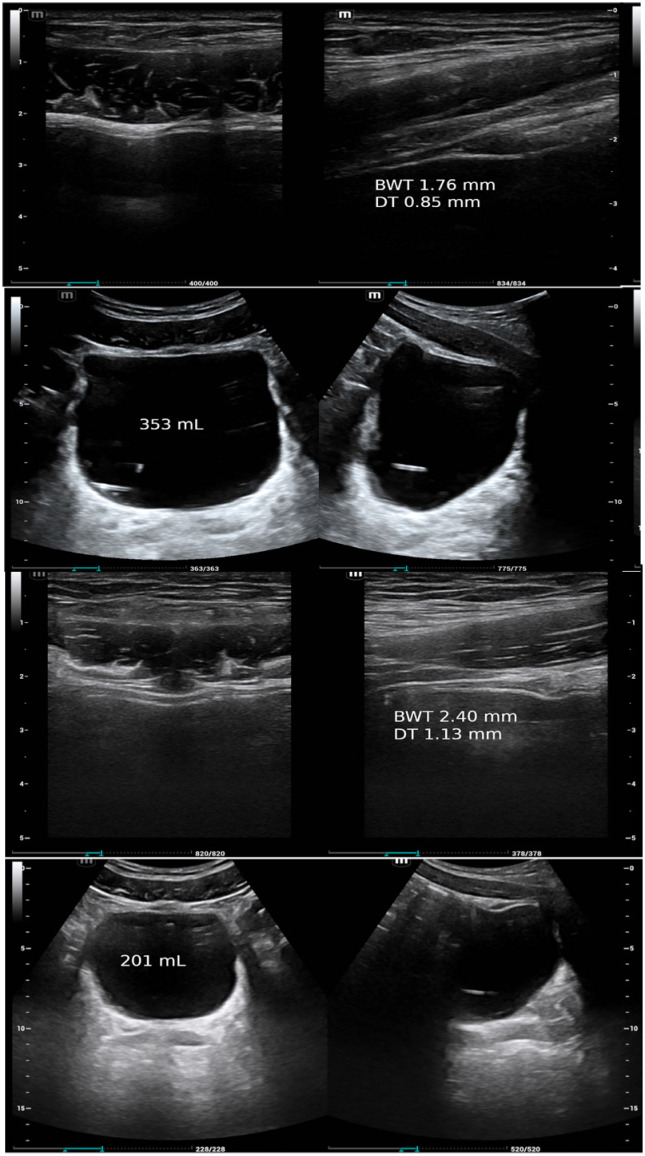

超声估计空后残尿患者膀胱和逼尿肌重量。

Ultrasonically Estimated Bladder and Detrusor Weights in Patients with Post-Void Residual Urine.